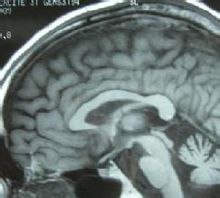

中医对小脑萎缩属于“萎症”等范畴的疾病,现代医学中又称脊髓小脑萎缩症,是一种家族显性遗传神经系统疾病,只要亲代其中一人为此疾病患者,其子女将有50%的机率遗传此症并发病。这类患者发病后,行走的动作摇摇晃晃,有如企鹅,因此被称为企鹅家族。 1、疾病简介 人的小脑的生理功能主要是维持身体平衡和协调随意运动。小脑病变时引发肌肉的张力低下,导致肢体打软,且对运动的距所需的力量估计不足,还会出现不规则的肢体震颤。 目前,仍不能完全揭示该病的病因,普遍认为并提出有效的治疗方此病病位在脑,中医则定位在肾,治疗在于补肾、益气、活血、健脑、豁痰、开窍。我们山东潍坊吉缘堂抗衰老中医药研究所贾学铭专家认为:小脑萎缩的发病根源不仅仅在肾,与其他脏腑器官功能的失调导致身体异常变化密切相关。对预防和治疗必须多方面的分析和治疗,才能达到治愈的目的。 (1)、自诊方法 自己是否患有小脑萎缩,可以用以下简易自我检查方法。 1.自然站立,双脚并拢,最后闭目,检查是否平稳。 2.在一直线上,脚跟挨着脚尖向前行走,观察动作是否平顺。 3.单脚站立,然后闭目,看是否平稳。 (2)、诊断要点是什么 小脑萎缩的诊断要点 小脑萎缩容易误诊为其他神经疾病,例如多发性硬化症。 确诊小脑萎缩的方法之一,是利用核磁共振成像(MRI)扫瞄脑部,可以见到病变进行中的小脑萎缩。 小脑萎缩最精确的诊断法,就是DNA分析,可以分辨本症的不同类型。 不是所有类型的脊髓小脑萎缩症都会遗传,所以患者的子女可以接受DNA检查,以便得悉他们会否有发病的危险。 (3)、症状 小脑萎缩的症状分为初期、中期和晚期三个阶段。

小脑萎缩(见右下方部分) 初期表现症状 ①走路犹如喝醉酒(眩晕感)。 ②动作反应较不灵活,动作的流畅性丧失,提重物有困难。 ③上下楼梯双腿不协调,肌肉僵硬,无法精确的完成某些特定动作,如跑步、爬山、打球等。 ④静止站立时,身体会前后摇晃,端水时容易溅出。行走时容易撞到墙上或门框上。 ⑤眼球转动有障碍,无法快速的转移目标。 ⑥辨别距离能力不良,如打不到乒乓球。 中期表现症状 ①四肢、肌肉不协调感加重,运动失调现象明显。 ②无法控制姿势与步伐,状似企鹅行走;摇摇晃晃,两腿微张或剪刀步,无法保持平衡,无法长距离行走,无法跑步,上下楼梯困难,走路时身体无法灵活调整。因此,容易摔跤。 ③舌头打结、说话不清楚,写字有困难,吃东西或喝水时容易被呛。 晚期现象 ①说话极不清楚,无法控制音调,甚至无法言语,写字无法辨认,吞咽困难。 ②无法站立,甚至无法坐起,需靠轮椅代步,或卧床在床,生活无法自理。 ③如果大脑或周围神经受到波及,则病人智力会受到影响。 (4)、以往医学研究认为与我们的研究有所不同 脑髓空虚是小脑萎缩的基本病理变化,中医理论认为肾气肾精亏虚是其基本病机。大量的实验和临床研究表明,老年肾虚者大多脑功能下降,大脑神经细胞减少,递质含量及递质受体数量均下降,内分泌功能紊乱,免疫功能下降,自身免疫和变态反应增加,体内自由基的容量及过氧化物随年龄增加而积累,而抗自由基损伤的物质如SOD含量下降。这些变化说明肾虚是老年性痴呆的重要病因。以肾虚为主要病机,以补肾填精益髓为治疗大法组方治疗。 我们认为预防和治疗小脑萎缩是需要调理脏腑为主是非常重要的,通过临床治疗其效果比以补肾精益脑髓的方法更好。(在小脑萎缩的调理治疗有细述) (5)、预防及注意事项 1.生活须规律,早睡早起,不熬夜。2、不要固定在相同的姿势太久,应该常变换姿势及活动方式。3、整个白天活动太累的话,中午尽量卧床休息一会儿。但如果晚上睡眠不太好,则切忌午睡太长。4、每天安排一些例行的事情做,让自己必须用心力去完成任务,有点困难更好,如娱乐、工作等,可以提高士气,制造生活乐趣或成就感。5、春夏季节早睡早起,秋冬季节早睡晚起,以顺应自然界的四时气候变化。 2.饮食不要太讲究,最好是自然食物形态。不要过度加工,食物添加剂越少越好。2、各种蔬菜水果轮换着吃,以吸收不同的营养成分。每天1个鸡蛋、2大杯牛奶。多食鱼类与海产,适量肉类与豆制品。不吃油炸、油酥、辛辣、腌渍、罐头汤、奶油、番茄浆、香肠、腊肉、热狗、蛋糕、洋芋片。咖啡、烟、酒、茶也要少用。最好的是纯水和鲜果汁。3、饮食要低盐、低糖、低脂肪。4、营养要均衡,不要暴饮暴食。 3.调摄精神,清心寡欲:保持愉快和乐观的情绪,避免精神过度紧张,思虑过度,应清心寡欲,恬淡虚无,清静内守,精神自持,遇事豁达,心胸开阔,不斤斤计较,不贪心过度,保持安静平和的心态,尤其是中老年人,更应如此。 3.药物调理,延缓衰老:对于50岁以上的老年人,尤其是有脑萎缩遗传性家族史的病人,更有必要在50岁左右选择运用延缓衰老的中药调理,以改善脑细胞衰老的状况。 4.明确病因,预防发病:对于病因较为明确者,针对病因进行预防,尽早祛除致病因素。如积极预防脑血管病,防止或尽可能的延缓脑动脉硬化的发生;脑部的感染性疾病,宜预防其发生,对已发生者宜及早治疗;避免过量过久使用对脑组织有损害的药物;早期切除颅内肿瘤;防止滥用酒精及过量饮酒等,有效的防止可逆性脑萎缩的发生。而对于外伤引起的脑组织损伤,应及时有效的治疗。 5.均衡营养,少荤多素:调整饮食,饮食宜清淡而富含营养,少食肥甘滋腻之品,以高蛋白和高维生素饮食为主,多食蔬菜和水果及含碘食物,注意营养均衡,禁酒戒烟,养成良好的饮食习惯。 6.劳逸结合,适度锻炼:避免过度疲劳,适当参加一些力所能及的体力劳动和体育运动,以增强体质,增强机体的抗病能力,也要有充分的睡眠和休息,同时每天可做一些太极拳或气功之类的训练,促进机体的气血运行,增加脑部的血液循环和血氧供应。 以上内容即为小脑萎缩的有效预防措施,对于有发生小脑萎缩高危因素的患者,采用上述预防措施,则更具有其重要意义,尤其是有家族遗传病史者,更应加紧预防本病的发生,以减少该病的患病率或延缓发病时间,提高生活质量,减轻家庭和社会的压力;而对于已发生脑萎缩的患者,给予患者适当的、符合患者个体差异的正确护理,则有利于患者配合治疗,减缓疾病的发展速度,使疾病尽快向好转方向转化。 有家族史还没有出现明显发病时,就应该用中药早期调理治疗,以预防小脑萎缩的发生。 网址:www.jiyuantang.cn 山东潍坊吉缘堂抗衰老中医药研究所 |